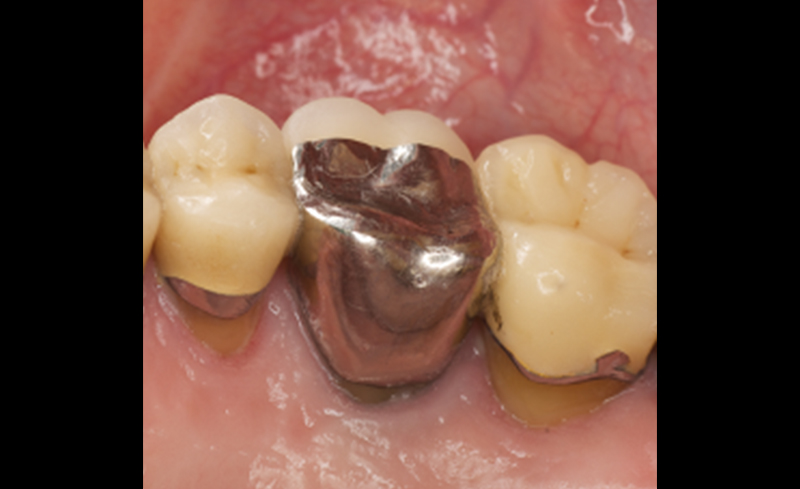

虫歯や審美的な目的で被せ物(クラウン)の治療を行う場合、残っている歯の高さが重要です。この高さ多ければ多いほど、被せ物の内面の接着面積が増え、外れにくい構造になるからです。

また、残っている歯のマージン(歯の縁)が確実に歯茎から出ていることも重要です。マージンが歯茎で隠れていると、被せ物の型取りが上手くできず、正確な被せものができないからです。

| 治療内容 | 初診時に左下の被せ物がとれて来院されました。根の治療後に、歯冠長延長術を行い被せ物をしました。 |

| 年齢 | 26歳女性 |

|---|---|

| 治療内容 | 初診時に左下の臼歯部の被せ物が外れて来院(左図)。根の治療後に、歯冠長延長術を行い被せ物をしました(右図)。 |